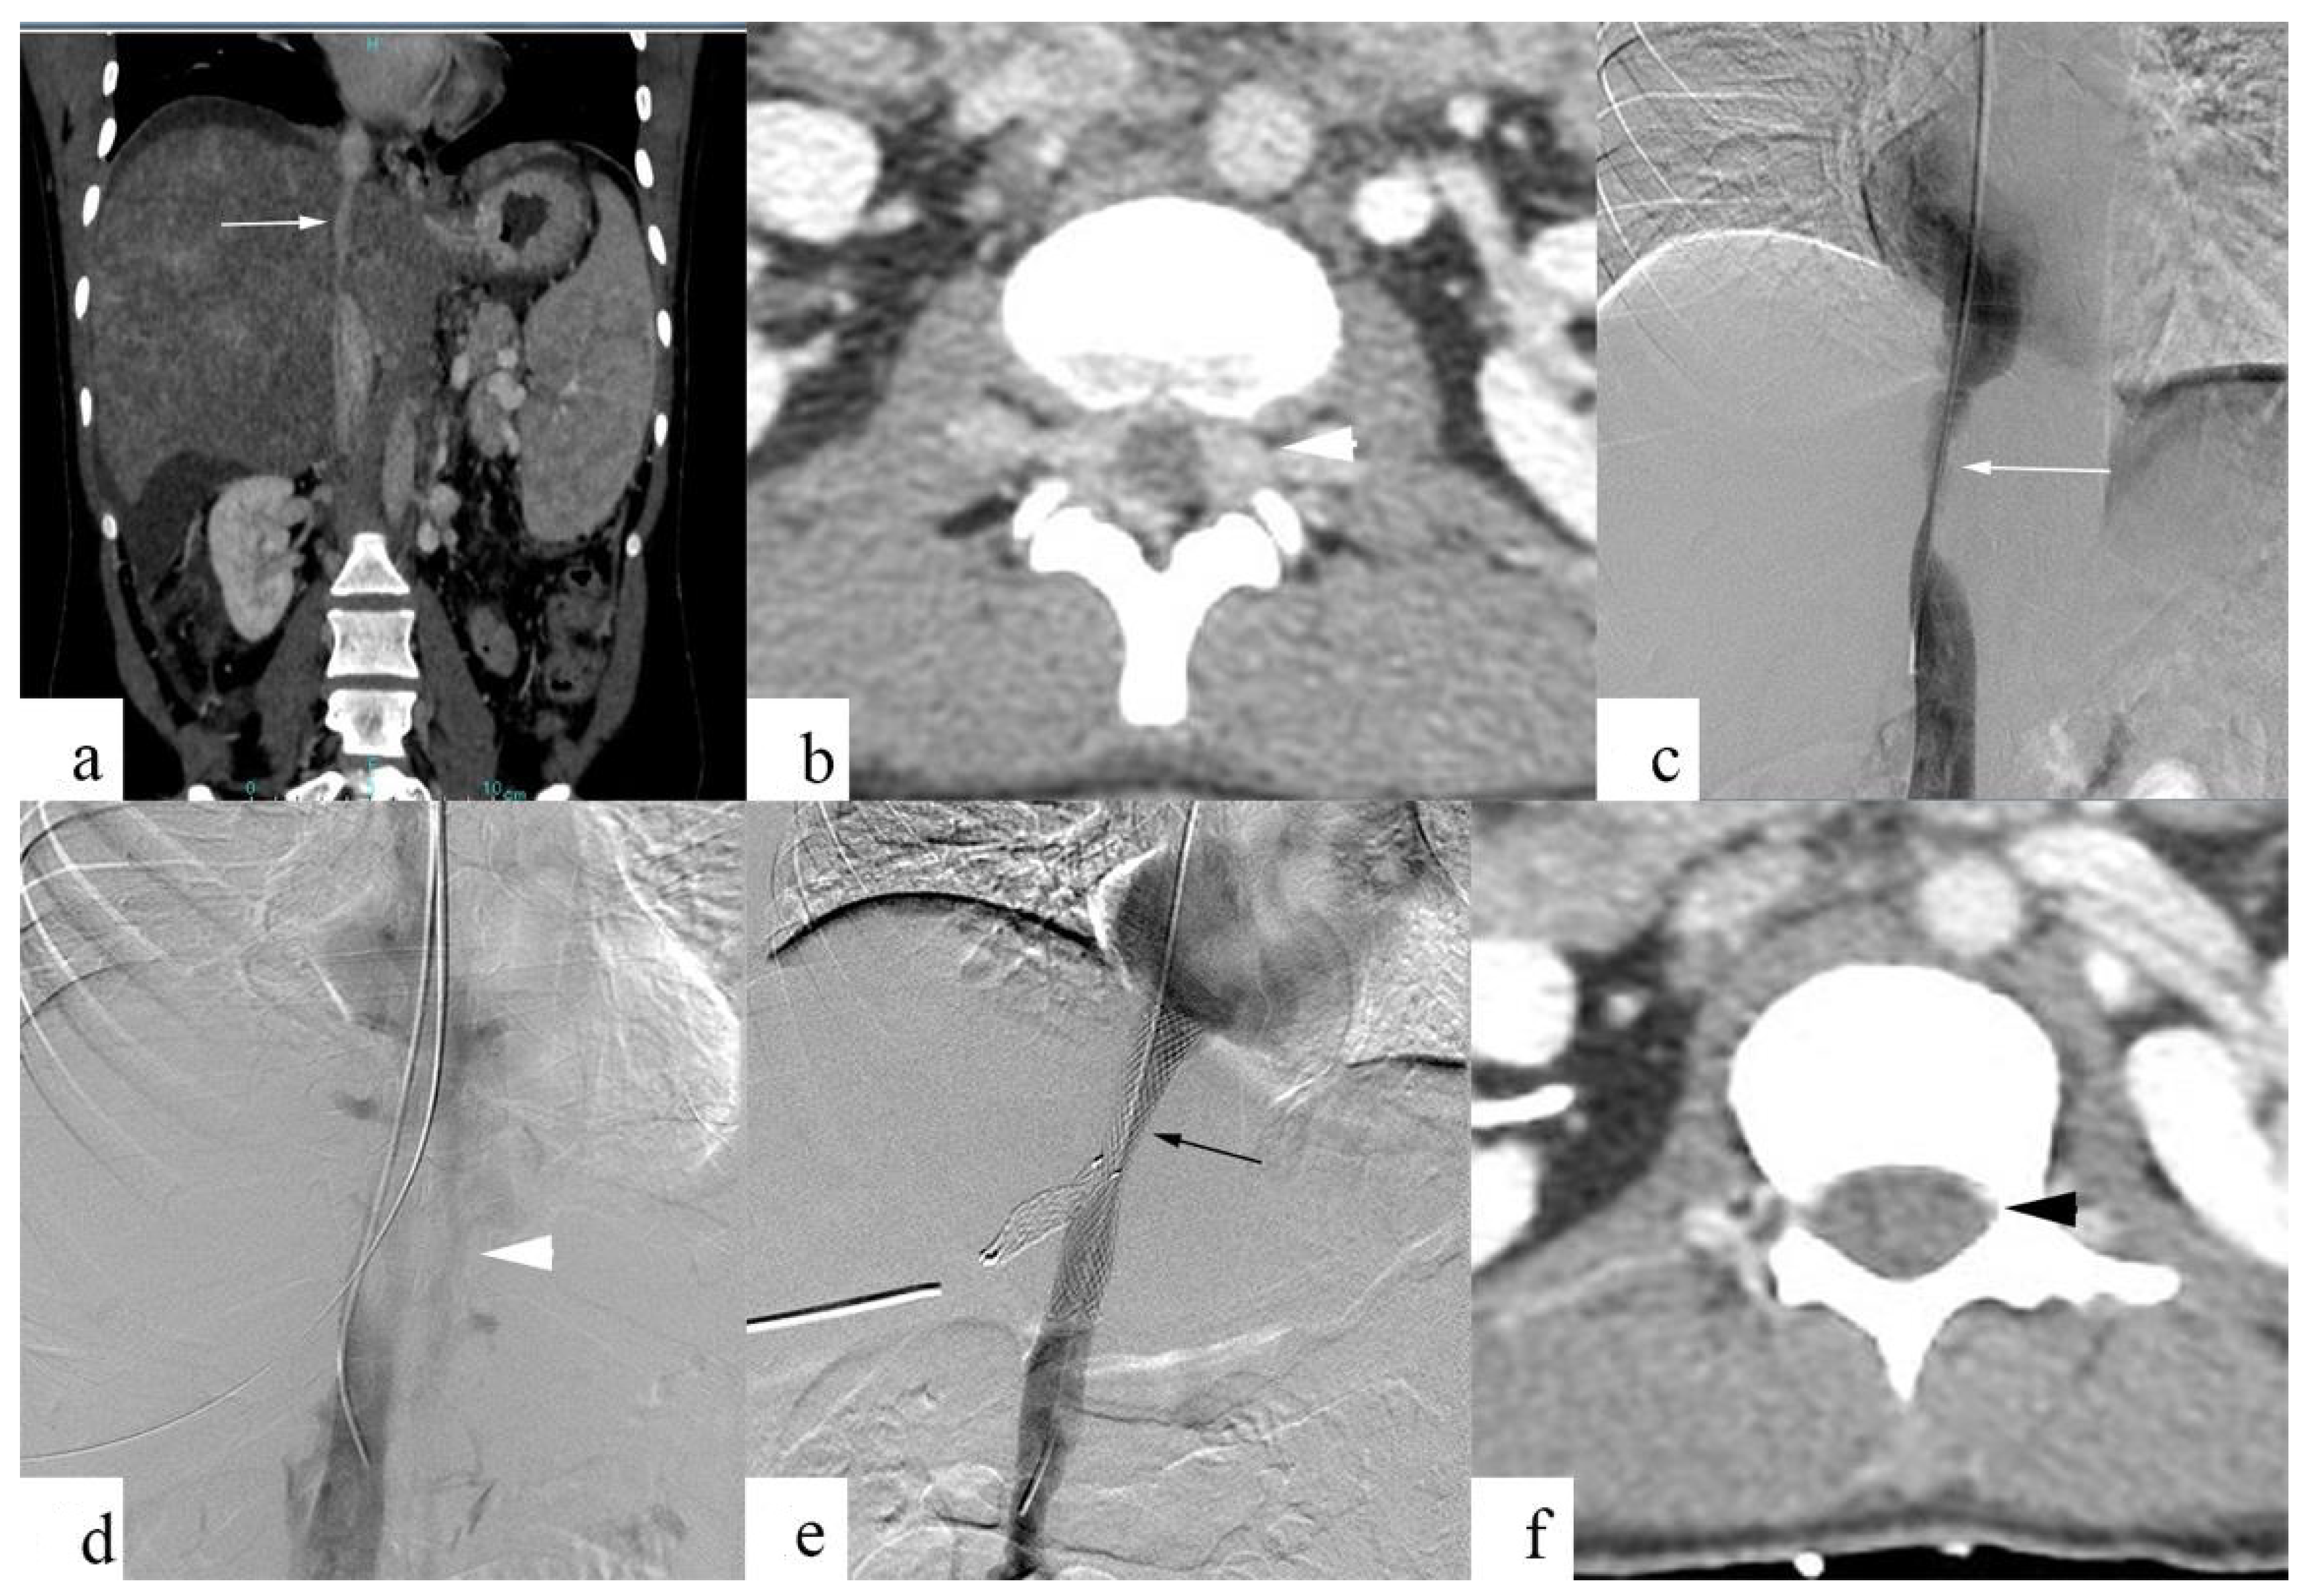

3. Results

Evaluation of Back Pain